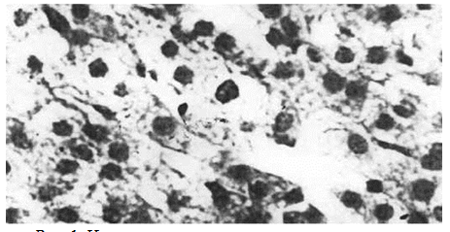

Надпочечники животных опытной группы. Через 5 часов после иммобилизационного стресса отмечается отек капсулы надпочечников и разволокнение и набухание коллагеновых волокон. В капиллярах полнокровие и стаз. Выявлялись дистрофические изменения эндотелия артериол и венул капсулы. В перикапиллярном пространстве обнаруживались инфильтраты. Среди клеток инфильтрата преобла-дали лимфоциты и гистоциты. Цитоангиоархитектоника органа была нарушена. Отдельные участки, в которых сохранялось зональное распределение адренокортикоцитов, чередовались с полями, в которых граница между конкретными зонами коркового вещества контурировалась нечетко. Именно в этих участках весьма отчетливо прослеживались дистрофические процессы. Следует отметить, что клетки клубочковой зоны теряли характерную структурную ориентацию и располагались относительно компактно по всему периметру надпочечника. Как правило, в клубочковой зоне доминировали темные ацидофильные клетки. В то же время в участках дистрофии наблюдалась выраженная дискомплексация адрено- кортикоцитов пучковой зоны. Адренокортикоциты теряли характерную линейную ориентацию и способность формировать эпителиальные тяжи (рис.1).

Рис. 1. Надпочечник, признаки дискомплексации и дистрофии адренокортикоцитов. Окраска гематоксилин- эозином, об. 40x10

Причем явления дискомплексации секреторных клеток с наличием единичных некротических микроочагов обнаруживались преимущественно в поверхностных участках пучковой зоны. Весьма четко пролеживались явления перераспределения липидов в корковом слое надпочечников. На всем своем протяжении граница между клубочковой, пучковой и сетчатой зонами не контурируется. Лишь в отдельных участках обнаруживаются клубочки. Клубочковая зона выглядит резко суженной за счет расширения границ пучковой с сетчатой зон. Следует отметить, что адренокортикоциты пучковой зоны на значительном протяжении теряли способность формировать характерные эпителиальные тяжи. Повсеместно встречались очаги микронекроза. Адренокортикоциты представлены исключительно светлыми гипертрофированными клетками, цитоплазма которых выглядела оптически светлой и резко набухшей. Границы между отдельными смежными клетками контурировались нечетко.